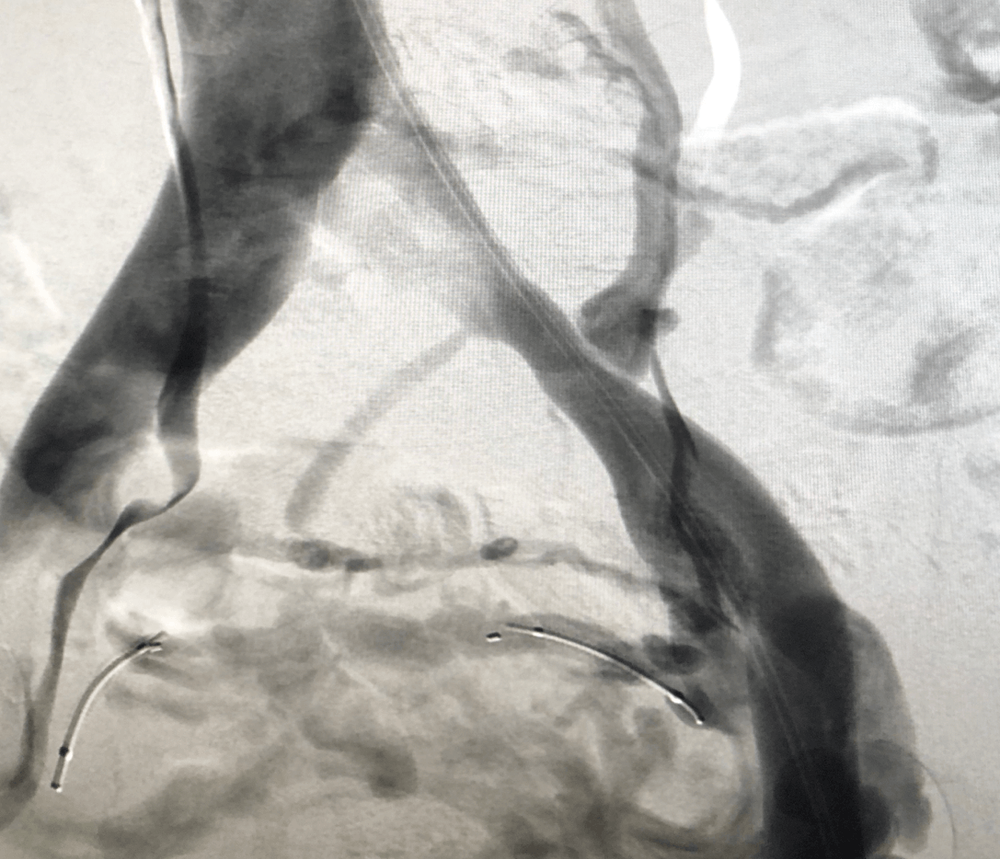

Diagnosis can be made using ultrasound or laparoscopy testing. The condition can also be diagnosed with a venogram, CT scan, or an MRI. Ultrasound is the diagnostic tool most commonly used. Some research has suggested that transvaginal duplex ultrasound is the best test for pelvic venous reflux.

More advanced treatment includes a minimally invasive procedure performed by an Interventional Radiologist. This minimally invasive procedure involves stopping blood within the pelvic varicose veins using a minimally invasive procedure called a catheter directed embolization. The procedure rarely requires an overnight stay in hospital and is usually performed as an outpatient procedure, and is done using local anesthetic and moderate sedation. Patients report an 80% success rate, as measured by the amount of pain reduction experienced.